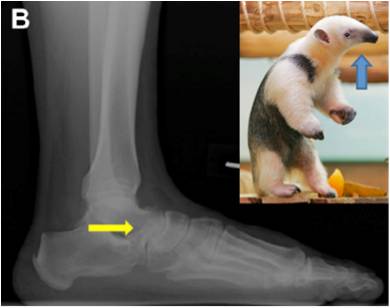

放射学特征:跟距联合在侧位X线片上呈现C sign,跟舟联合在侧位X线片上呈现食蚁兽鼻征 拍摄45°内斜位X片观察跟舟联合。跟骨轴位(Harris and beath): 跟骨轴位X线片观察跟距联合。